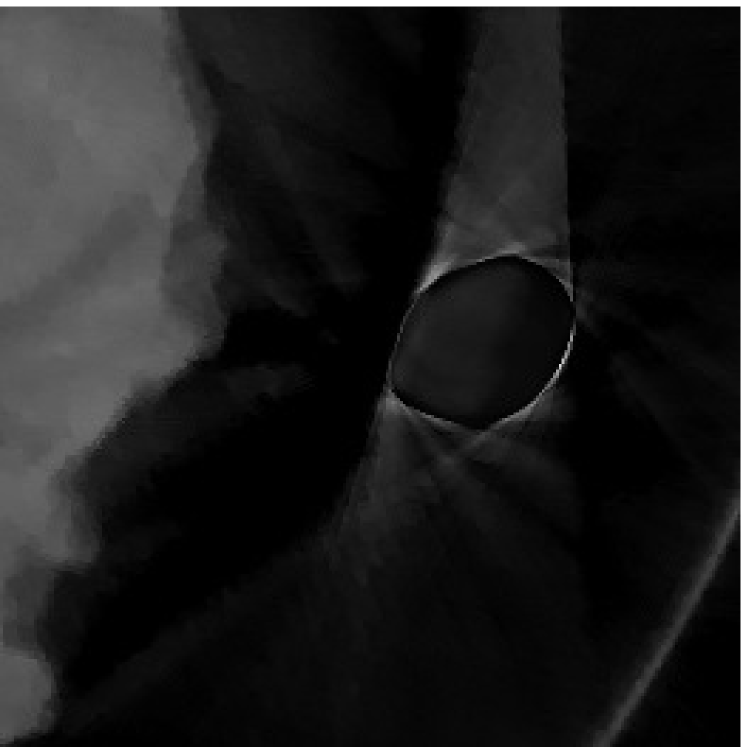

where is the restriction operator with respect to the domain . The restriction operator is defined as: for ; and for . The optimization problem (2.13) can be solved similar to (2.12) by the split Bregman algorithm. We denote the solution of (2.13) as (Figure 2(a)).

The weights will be computed by projecting a segmented image that approximates tissue classification of the unknown CT image. One may obtain such approximated tissue classification by segmenting image obtained from (2.12) or obtained from (2.13). However, the approximation from either image will be rather inaccurate since has severe artifacts in between metal locations (Figure 1(b)), while the metal components are missing from (Figure 2(a)) though there are less artifacts in between metal locations. Therefore, we propose to segment a combined image defined by

with a tuning parameter. In this paper, the segmentation of is obtained by the algorithm proposed by [34, 35]. The segmented image, denoted as (Figure 2(b)), contains three components: the air, the low density components such as soft tissues, and the high density components such as bones and metals. The intensity values of the segmented image from prior image are assumed to be constant for each segmented component. We propose to use the mean values of in the segmented regions as the constants. After obtaining , the weight that will be used in our re-weighted JSR model is defined by . Finally, we note that the reconstructed image using the re-weighted JSR model is relatively insensitive to the choice of the parameter in (2.14), which is demonstrated in Table 2 using NCAT phantom.